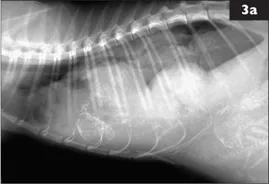

3 A 3-year-old female DSH cat is presented for 1 week of lethargy and increased respiratory effort. She is at 56 days of gestation. A similar episode occurred with the previous pregnancy and responded favorably to antibiotic therapy. This episode seems to be worse. Right lateral (3a) and DV (3b) thoracic radiographs are made.

i. What radiographic abnormalities are evident?

ii. What is the radiographic diagnosis?

3 i. There is increased opacity in the ventral and right halves of the thoracic cavity. Only a short dorsal segment of the left crus of the diaphragm is distinct; the remainder is effaced by the increased thoracic opacity. The trachea is displaced dorsally, but remains mid-line in the DV view. The heart is shifted dorsally and to the left. Only the left lung lobes are well inflated with well-defined vessels. The increased thoracic opacity is a mix of solid soft tissue or fluid and mineralized opacity of fetal skeletal structures. A fetal skull is evident ventrally at the 5th intercostal space and a different fetal lumbar spine crosses the pleura-peritoneal junction ventrally.

ii. Right-sided diaphragmatic hernia with thoracic displacement of gravid uterus and probably liver. The degree of fetal skeletal mineralization is consistent with late-term gestation. No signs of fetal death are evident. Ultrasound would be valuable to determine fetal viability. In several reports, the most common organs to be herniated through a tear in the diaphragm are liver, stomach, and small intestine. Several case reports of diaphragmatic herniation of gravid uterus in dogs appear in the literature.